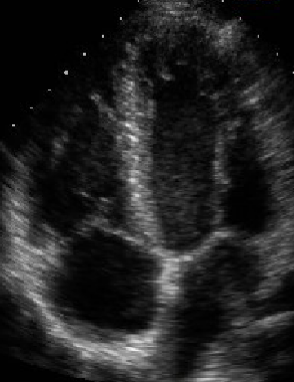

<p>What view is this?</p>

What view is this?

Apical 2 Chamber